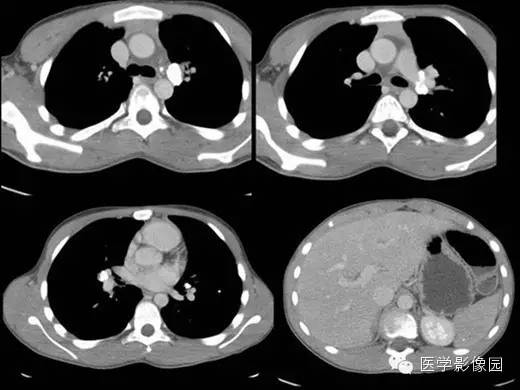

【病例】组织胞浆菌病1例CT影像表现

主要分布在美国密西西比河和俄亥俄河流域,国内报道较少。本菌所侵犯的各器官,病理改变基本一致。开始为中央部分增生,吞噬细胞内有或多或少的真菌。其后发生组织坏死,周围呈肉芽肿样变化,最后则愈合或纤维化。原发性接触性组织胞浆菌病呈非特异性炎性浸润,间或可见有巨细胞及坏死区。

X线检查、CT:可见肺、肝、脾等脏器可有许多钙化点。纵隔组织胞浆菌病还包括纵隔的肉芽肿和纤维化性纵隔炎。组织胞浆菌病大多数不需要特殊治疗,通常经过卧床休息、加强营养等支持疗法后,多在3个月至数年间自然痊愈。